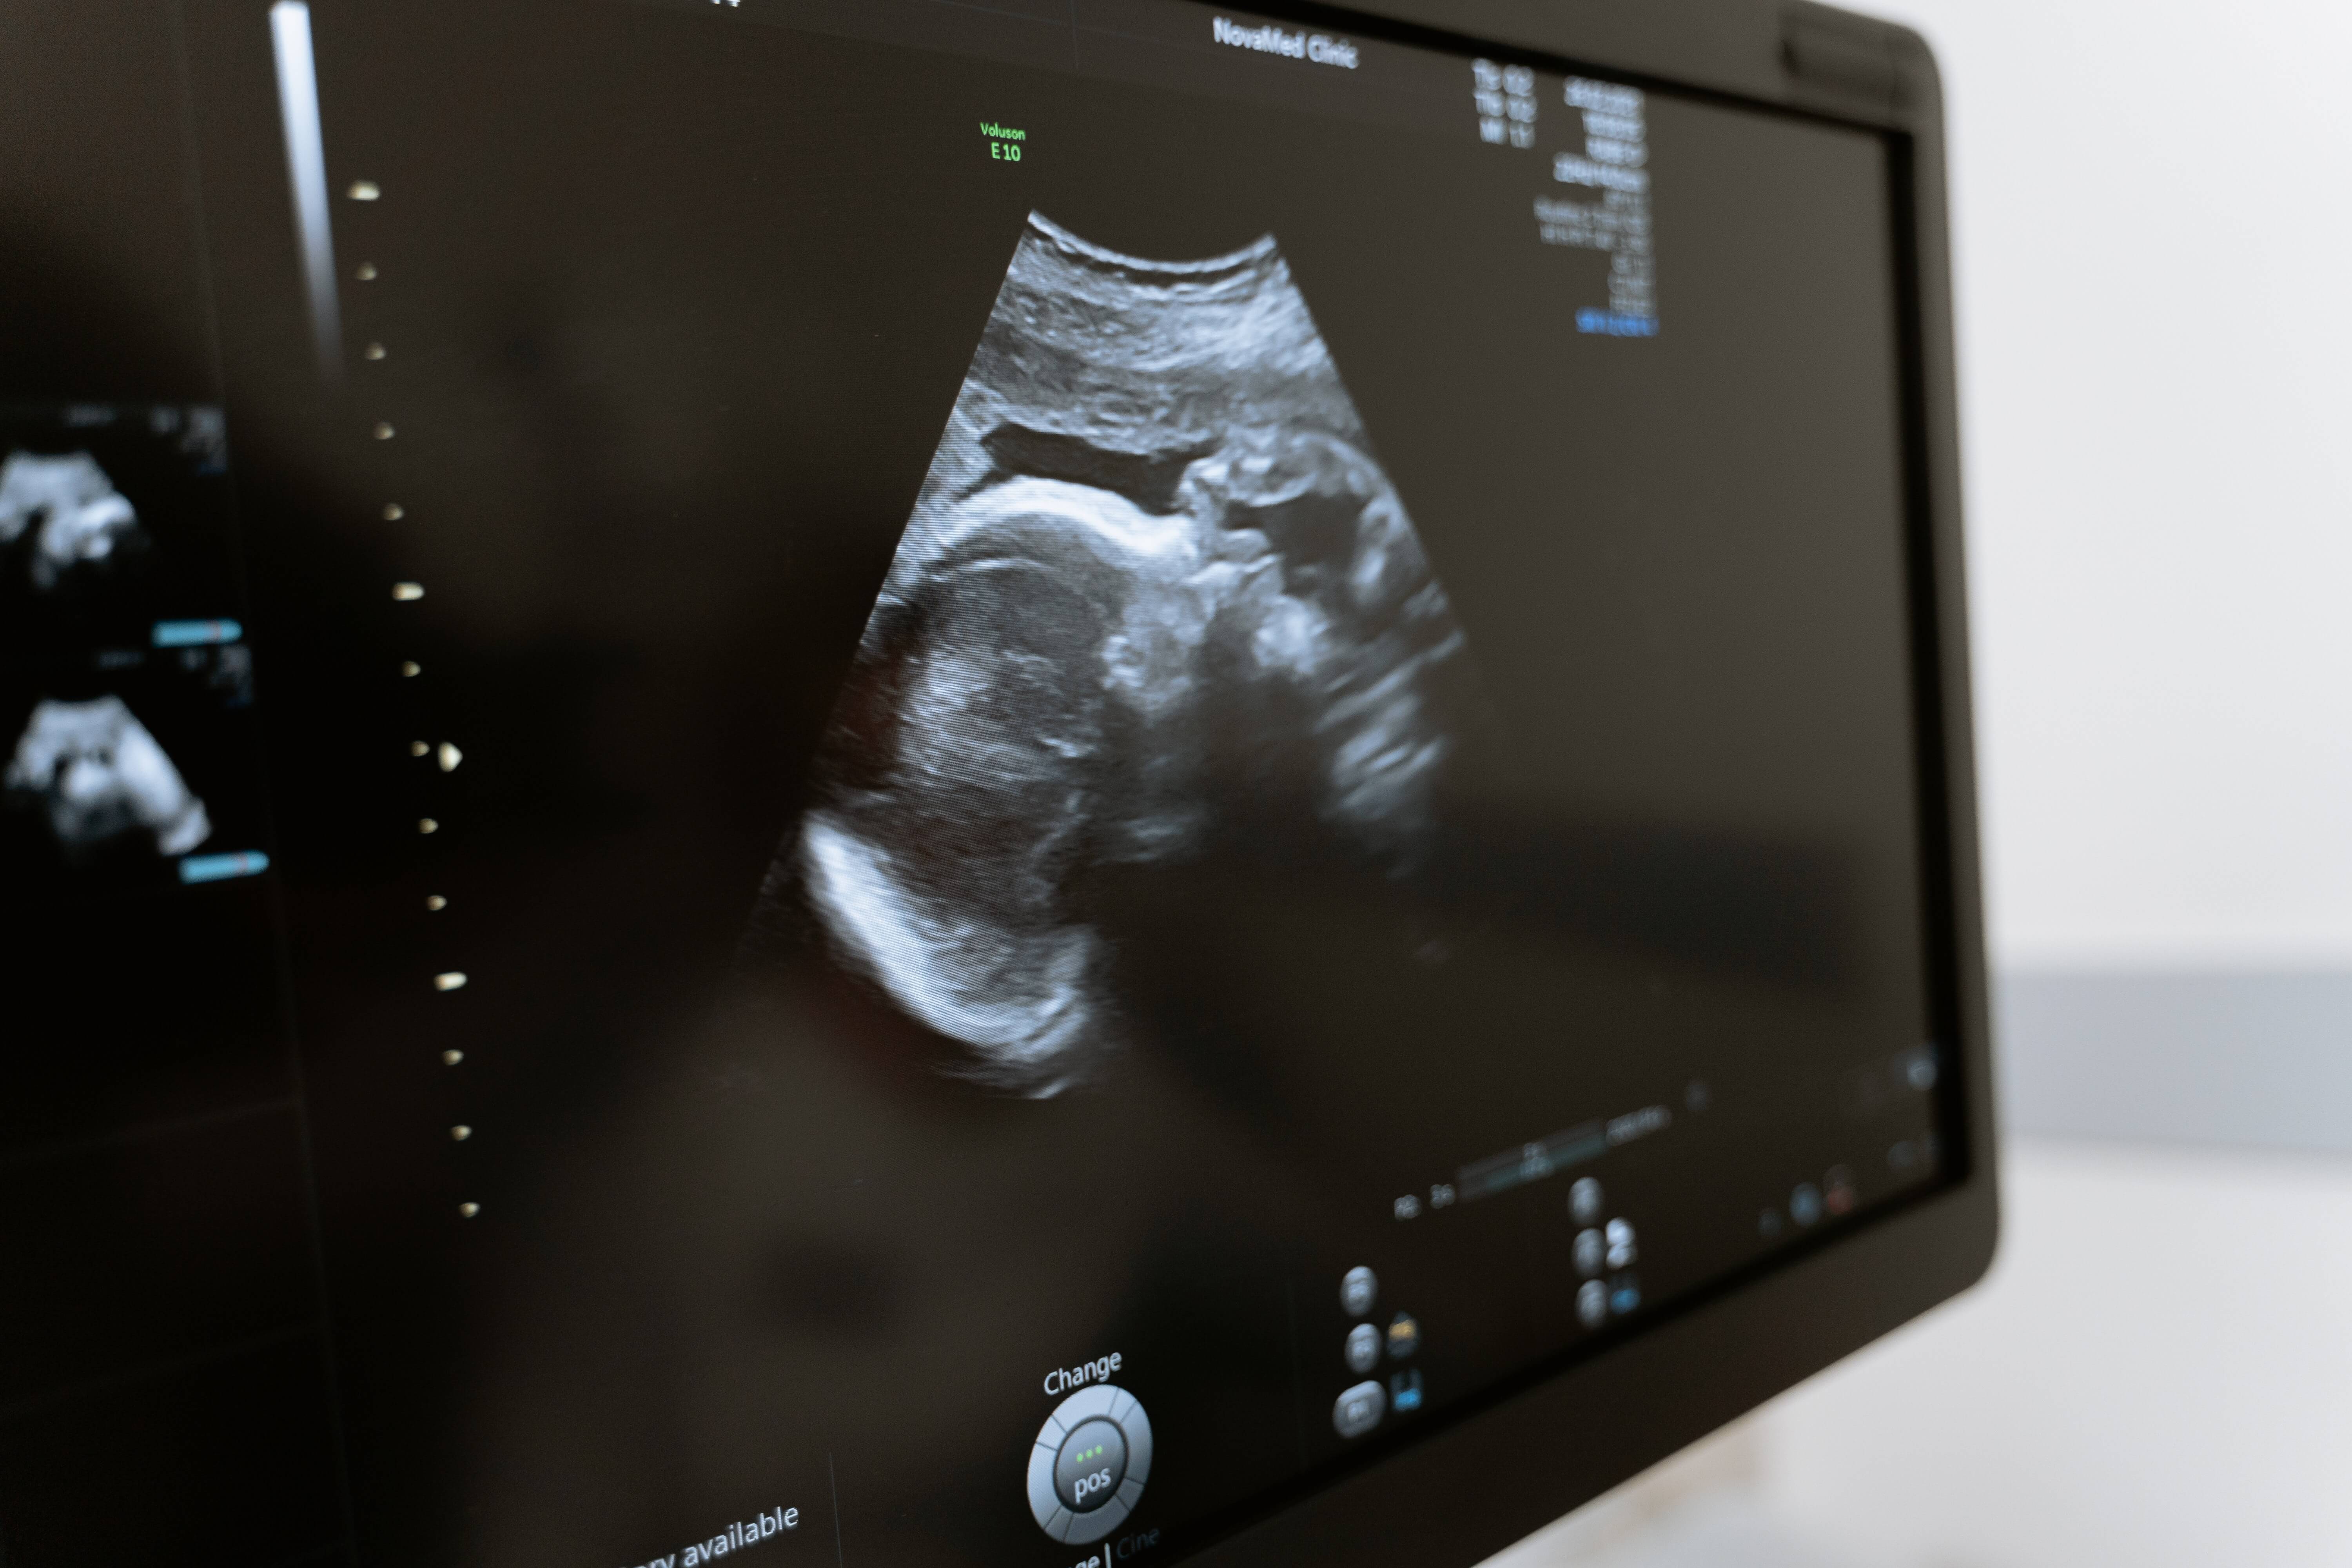

임당검사와 정밀 초음파가 예정되어 있었습니다.

아기 얼굴을 자세히 볼 수 있는 입체초음파는 다음번 방문했을 때 할 예정이라고 하네요.

다음 입체 초음파를 위해서는 물을 많이 마시는 것이 중요하다고 합니다.

입체초음파를 진행할 때는 아기가 많이 자라서 예쁘게 나오지 않는 경우가 있으니

꼭 물을 많이 마시도록 합시다!!